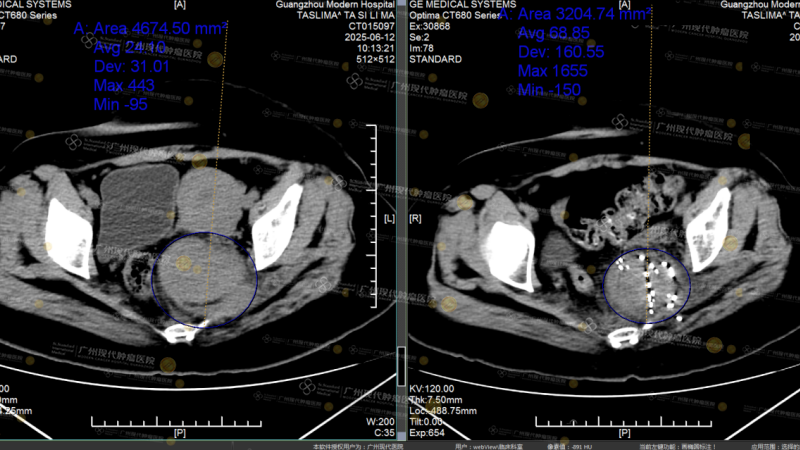

Đồng thời, bác sĩ còn phối hợp sử dụng thuốc nhắm trúng đích nhằm kiểm soát tiến triển của bệnh và duy trì trạng thái toàn thân. Theo thời gian, mỗi lần tái khám chẩn đoán hình ảnh lại mang đến một tin tốt hơn: khối u dần thu nhỏ, bên trong bắt đầu xuất hiện tình trạng hoại tử. Những thay đổi ấy khiến cả gia đình chúng tôi cảm thấy yên tâm hơn rất nhiều.

Hình ảnh CT trước và sau điều trị

Sau khi cẩn thận xem lại những hình ảnh kiểm tra mới nhất của em, bác sĩ đã đưa ra một kết luận vừa vững chắc vừa nhẹ nhàng: đánh giá hiệu quả điều trị đạt mức thuyên giảm một phần (PR).